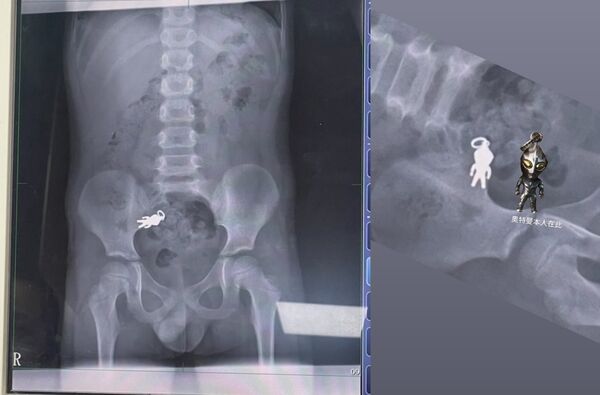

▲X光片顯示宜蘭7歲男童誤吞的奧特曼吊飾。(圖/翻攝自threads,下同)

宜蘭一名7歲男童日前吃餅乾時不小心將「奧特曼吊飾」吞進肚子,家人緊急帶他到醫院檢查,X光片清楚顯示腹腔內有一個形狀完整的奧特曼。這則趣味十足的消息在網路上引發熱烈討論,不少網友笑稱,「奧特曼拉出來後會不會變成奧德賽?」

根據貼文者分享,男童當時一邊看電視一邊吃餅乾,結果不小心把手上的奧特曼吊飾吞下肚。他的家人隨後帶他到羅東博愛醫院檢查,負責診治的謝錦桐醫師透露,吊飾約2.8公分x1.4公分大小,目前已隨腸道蠕動到小腸,男童身體狀況良好,建議回家密切觀察是否能隨排便排出。

貼文者還幽默地將奧特曼吊飾與X光片上的影像擺在一起做對比,並標註「奧特曼本人在此」。此舉引發網友紛紛留言 有人笑說「史上第一個跟奧特曼合體的人」、「X光片可以裱框嗎?超酷的」,還有人調侃「奧特曼離開洞口會不會『ㄎㄧㄤ』一聲」。